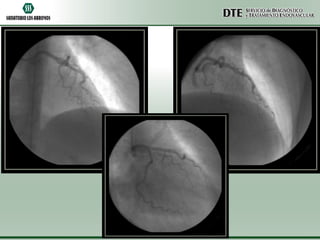

Cinecoronariografía

•Arteria descendente anterior de fino calibre y aspecto

hipoplásico.

•Arteria circunfleja y coronaria derecha sin lesiones

angiográficamente significativas.

•Acinesia de punta y segmentos apicales de pared anterior

e inferior.

•Moderado deterioro de la función sistólica ventricular

izquierda.